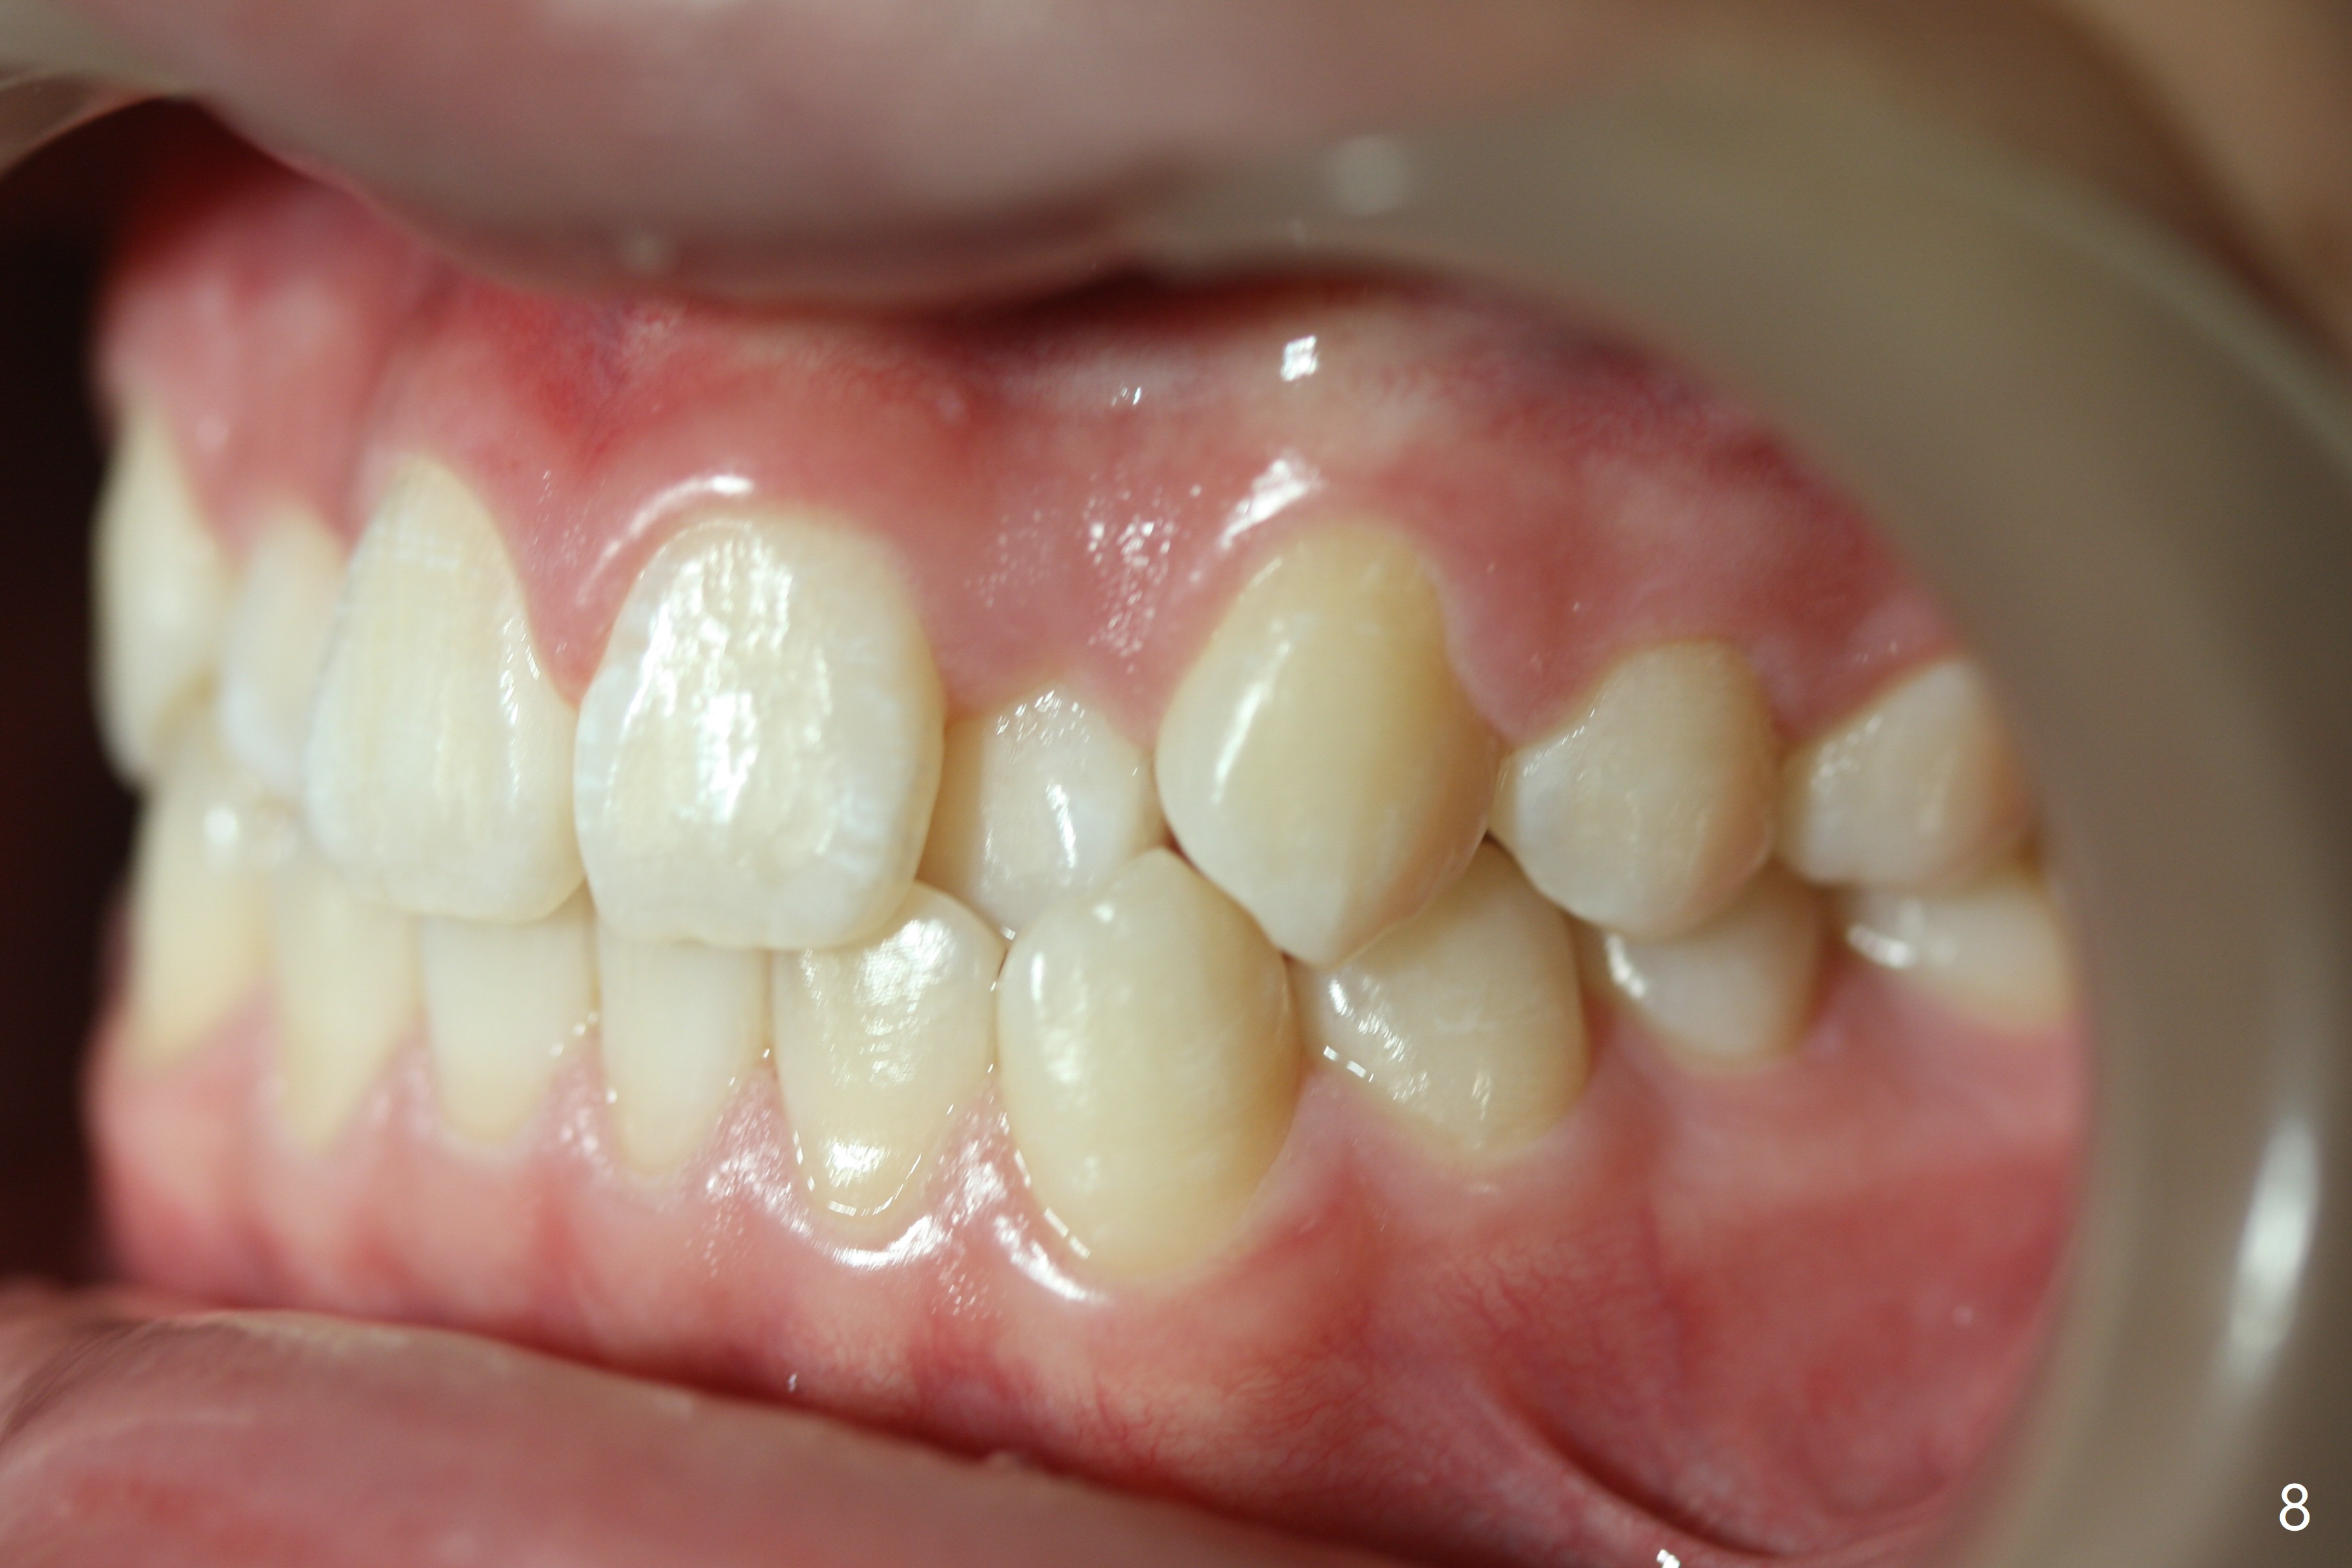

The upper dental midline of a 14-year-old man deviates the left (Fig.1,2,8) with midfacial concavity (Fig.3,4). The upper lateral incisors have cross bite, more severe on the left (Fig.6-8). Can we use open coil spring on the left first, a few months before the right, more or less to help correct the upper midline deviation? Cephalometric analysis shows Class III skeletal relationship (Fig.5,5',11).